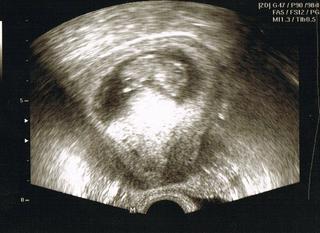

Ahoj holky... omlouvám se, že se ozývám až tak pozdě, ale teprve teď jsem se dneska dostala k PC. Miminko roste dobře má 3,8 cm a odpovídáme 10tt+3. Srdíčko krásně buší a brali mi dnes asi 6 ampulí krve na ten NT screening - který se sám dělá až v 13.týdnu - takže jsem objednaná na 8.6. To byly pozitivní zprávy pana doktora, no a nezapomněl jako vždy postrašit také tím, že s tím mým vysokým krevním tlakem to nebude sranda - no a nakonec hledal lék co beru v chytré knížce a tam se dozvěděl, že se tenhle lék nemá brát od 2. trimestru - že způsobuje problémy s placentou no a jeho užívání v 1. trimu není vlastně odsledováno... tak mám hrůzu - jestli něco nezpůsobil. No my nemůžeme mít nic úplně bez problémů. Nechápu proč jsem tedy hned jak jsem to zjistila mazala k doktorce se zeptat, zda ho můžu dál užívat a ta mi řekla, že ano. V pondělí k ní jdu a neodejdu dokud mi to nezmění na variantu, kteerou mi navrhl gynekolog.

Ještě přikládám fotečku a dávám jí i do albíčka.